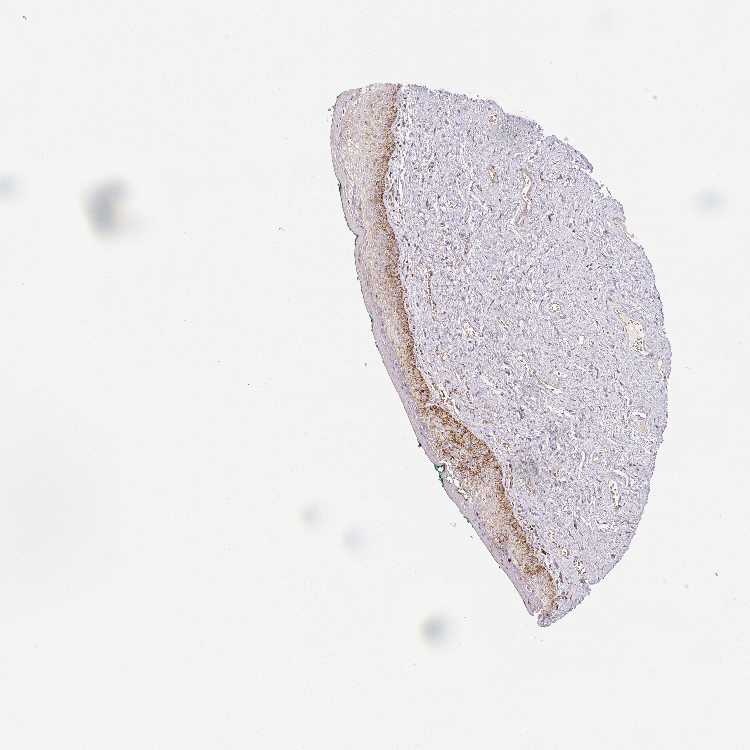

VAGINA - Antibody stainingi

Antibody staining in the annotated cell types in the current human tissue is reported as not detected, low, medium, or high, based on conventional immunohistochemistry profiling in selected tissues. This score is based on the combination of the staining intensity and fraction of stained cells.

Each image is clickable and will lead to virtual microscopy that enables deeper exploration of all samples and also displays staining intensity scores, fraction scores and subcellular localization as well as patient and tissue information for each sample.

Antibody HPA041981Antibody CAB034929

Squamous epithelial cells MediumNot detected